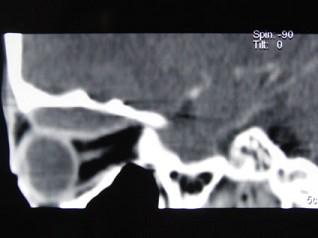

问题 男,12岁,有脓涕数年,发热约十天,伴右眼球向外下突出,CT如图,应诊断为 ( )

选项 A、眼型Graves病 B、肌炎型炎性假瘤 C、骨髓炎 D、骨膜下脓肿 E、转移瘤

答案 D